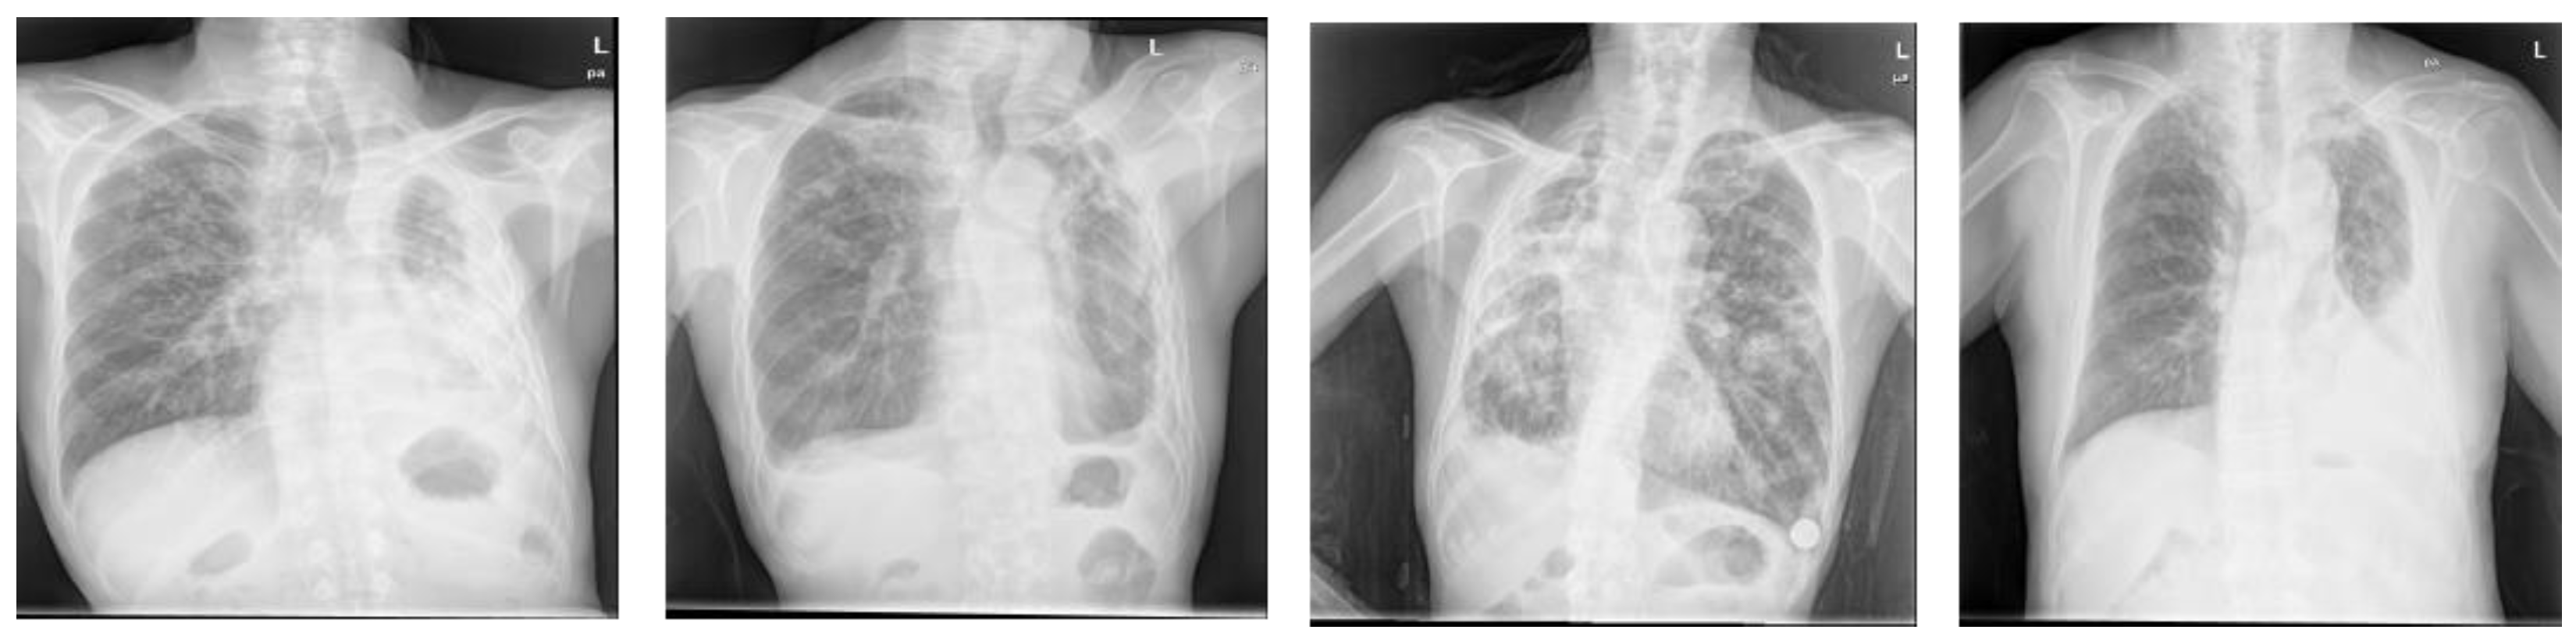

Figure 7.

Hard examples with deformed lung shapes or ambiguous cardiac silhouettes contained in the Shenzhen dataset.

When the network performance was compared by applying the attention module at various positions, the best segmentation performance was obtained when it was applied at the position, irrespective of datasets used. With the Montgomery dataset and the JSRT dataset, the segmentation performance varies by up to 2.5% and 1.4%, respectively, depending on the locations of the X- and Y-attention modules, whereas the performance gain was marginal with the Shenzhen dataset. The performance improvement observed at the position can be attributed to the fact that when the attention module is applied at the position, the attention map extracted through is used as the input of the attention module. The fine features can be highlighted by applying the attention modules consecutively rather than by applying and separately. Furthermore, as the image segmentation must generate results with the same size as the input image, the structure showed good performance. In general, initial layer features are typically more general whereas the latter layer features exhibit greater levels of specificity. Therefore, by locating attention modules in the initial layers, deep neural networks can take advantage of feature recalibration to improve the discriminative performance. This finding is consistent with the results of the empirical investigations conducted using SENet. Figure 5 illustrates examples of the chest X-rays and actual lung regions used for evaluation, as well as the lung segmentation images of three configurations that showed the best performance in the experimental results. On comparison of the Dice scores, the networks applying the proposed attention module achieved comparable or better performances than the other deep learning-based approaches (see Figure 6). When the Montgomery dataset or the JSRT dataset was used, the proposed method outperformed both standard U-Net and Attention U-Net. In the case of XLSor, however, both approaches showed similar segmentation performances but the proposed method worked relatively more stably. In the case of the Shenzhen dataset, although both XLSor and the proposed method achieved better performances than the standard U-Net and Attention U-Net, their performance gain was marginal. We conjectured that this result was attributed to high variability of lung segmentation masks due to the different lung shapes and borders in the Shenzhen dataset compared to the other two datasets [25]. In particular, the inclusion of X-ray images with deformed lungs or ambiguous cardiac silhouette as shown in Figure 7 will decrease the learning ability of deep learning models. The experimental results shown in Figure 8 also support this hypothesis.